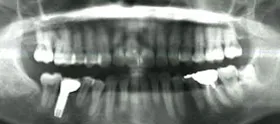

矯正、インプラントのための骨再生、歯の保存のための再生治療を組み合わせて治療を行った例

虫歯と重度の歯周炎(歯槽膿漏)、歯並びに悩まれていたケースです。

■初診時の全体写真

治療のポイント

歯並びを整え、咬合を回復するため、矯正治療を併せてを行いました。

歯が既に抜けていて、骨が吸収してしまっていた部分は、インプラントの埋入に十分な骨量を確保するための骨再生治療(GBR)を行いました。

歯周病によって、歯を支える歯周組織が破壊されてしまっていました。歯を保存するため、再生治療を行いました。

■治療前

■治療後

| 主訴 | 数年間、下の奥歯が無いため奥歯で咬めない 歯ならびが悪いため見た目が悪く口を開けて笑えないのとおいしく食事ができない 他院にて歯周病が治らないと言われた |

| 治療方法 | むし歯治療+骨再生療法(GBR)+矯正治療+インプラント治療+補綴治療 |

| 治療期間 | 約3年 |

| 通院回数等 | 約40回 |

| 費用 | 約500万円 |

| リスク・副作用 | 術後の腫れ・痛み |